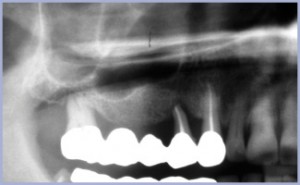

La foto 1 mostra la situazione pre-operatoria dove si evidenzia la grave situazione parodontale del 1.7 e del 1.4 che vengono estratti.

- Fig. 1